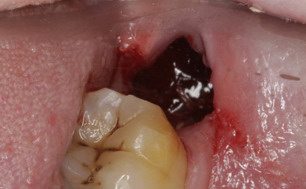

干槽症主要发生于下颌阻生智齿拔除后,是由口腔细菌引起的骨创感染,目前多认为创伤和感染及拔牙窝大是其主要病因。那么干槽症究竟有哪些危害呢?

反应性疼痛术后当日即出现,疼痛一般不严重,呈逐渐减轻趋势,3-5天内基本消失,检查拔牙创血凝块基本正常。而干槽症则是于拔牙后2-5天再次出现的剧烈疼痛,放散痛,持续时间长。

咽颊前间隙感染,术后疼痛,开口受限严重,伴有吞咽困难,下颌角内侧明显压痛,第三磨牙佘策下后方红肿、压痛,穿刺有脓液。而干槽症临床表现主要是剧烈的自发性疼痛,没有明显软组织肿胀,也没有脓液。

对于干槽症主要以预防为主。应重视减少手术创伤,保护血凝块,注意口腔卫生和术后适当休息。拔牙后在拔牙创内填塞各类抗感染、保护血凝块、减小拔牙创体积的物质,均能起到预防干槽症发生的效果。填塞物包括碘仿海绵、含有氯己定、抗生素的明胶海绵等。应做好术前准备,如清洁口腔卫生,术中做好消毒,减小拔牙创伤,避免大量唾液等污染物。术后做好护理,保护拔牙创血凝块,避免吸吮,戒烟,24小时内不能漱口。